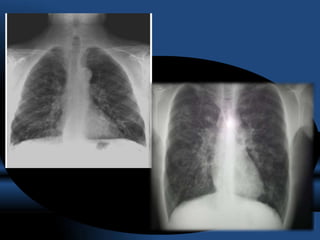

RADIOGRAFIA.

• La sensibilidad de la radiografía de tórax varia de un 45 a un 70% en relación

al diagnóstico de las bronquiectasias.

• Las bronquiectasias producen engrosamiento de la pared bronquial originando

el signo “ en raíles de tren” (tram lines).

• Acúmulo de secreciones a nivel bronquial ,“signos del dedo de guante”

• Imágenes quísticas, a veces incluso con nivel hidroaéreo y opacidades

anulares.

• El apelotonamiento de bronquiectasias quísticas en una zona pueden dar una

imagen similar a la del pulmón en panal.

• Atelectasias por obstrucción por tapones mucosos